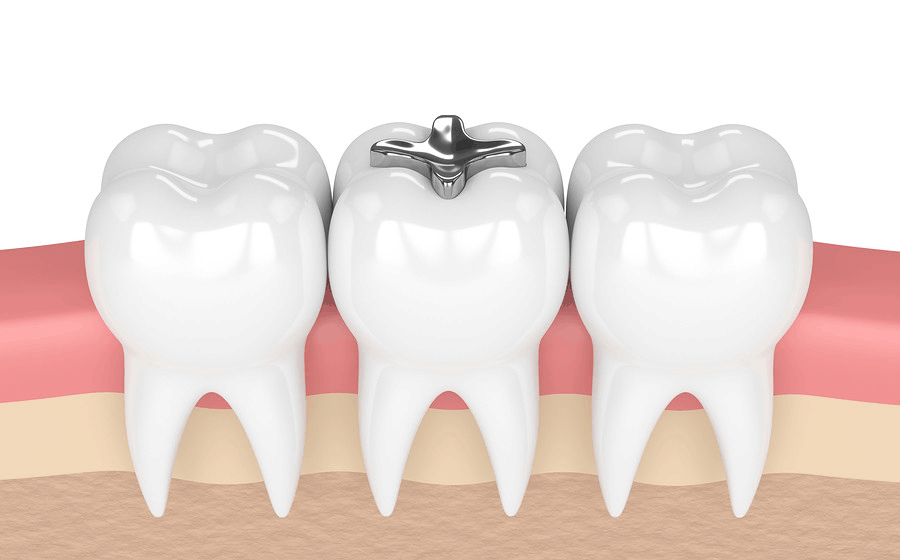

Dental amalgam is a filling material that has been used by dentists for over 150 years. A mixture of metals that typically includes silver, copper, and tin, dental amalgam fillings (often referred to as silver fillings or metal filings) also contain mercury, which has raised safety concerns among patients from time to time.

While composite (or tooth colored) fillings are more durable than ever thanks to advancements in technology, there are still many cases where amalgam fillings perform better (and longer). This is often the case with teeth that are naturally subjected to extensive chewing force, such as molars. Mercury is an important part of the amalgam mixture as it contains unique elements that allow it to be manipulated with ease during placement and then harden quickly after. In addition to the benefits of longevity, amalgam fillings are also more affordable than composites.

Composite fillings are typically made of a resin and glass mixture, tinted to the color of your tooth, and commonly referred to as white or tooth-colored fillings. They serve an important purpose for teeth that are visible when smiling, providing an aesthetic benefit not afforded by silver fillings.